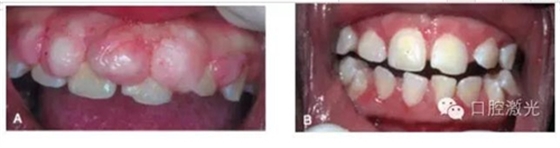

典型的激光口腔軟組織切除術(shù)當(dāng)場效果

牙齦部分增生激光切除前及1周后效果對比